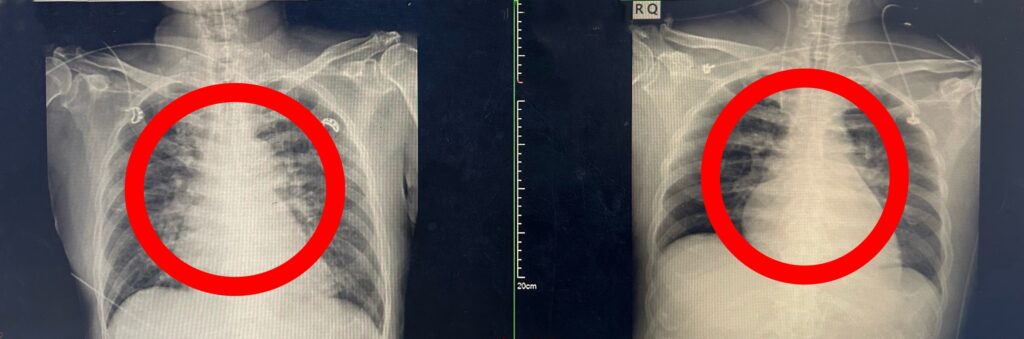

患者肺部發炎狀況。(記者孫義方攝)